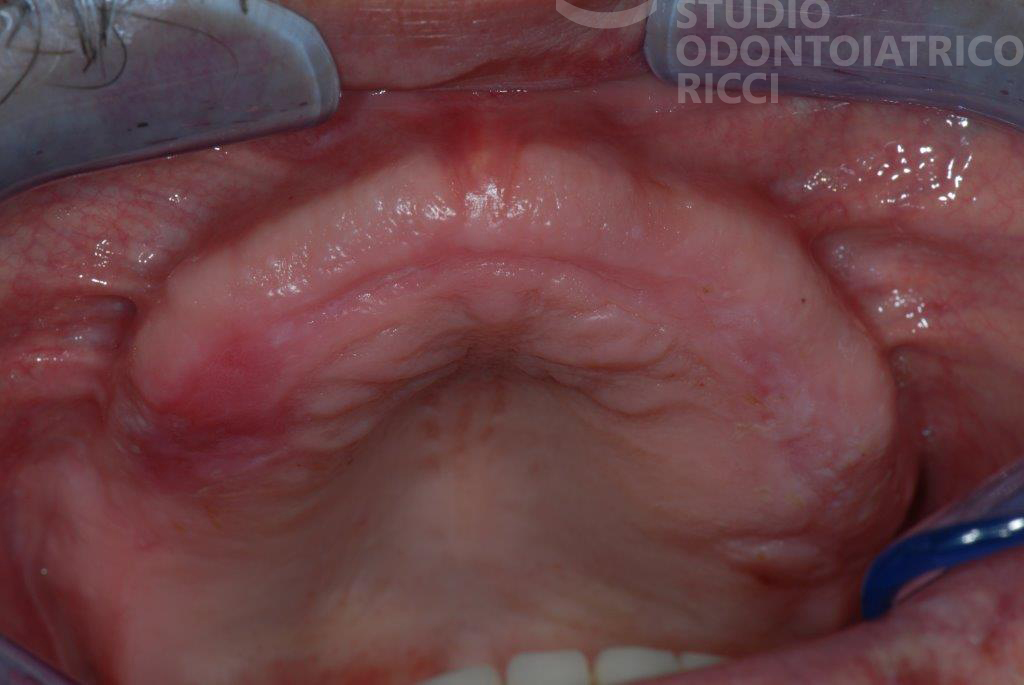

La maggior parte dei pazienti può sottoporsi a un trattamento implantare. È però fondamentale eseguire uno studio preliminare, con esami radiografici (es. TAC) per valutare:

quantità e qualità dell’osso

stato di salute generale